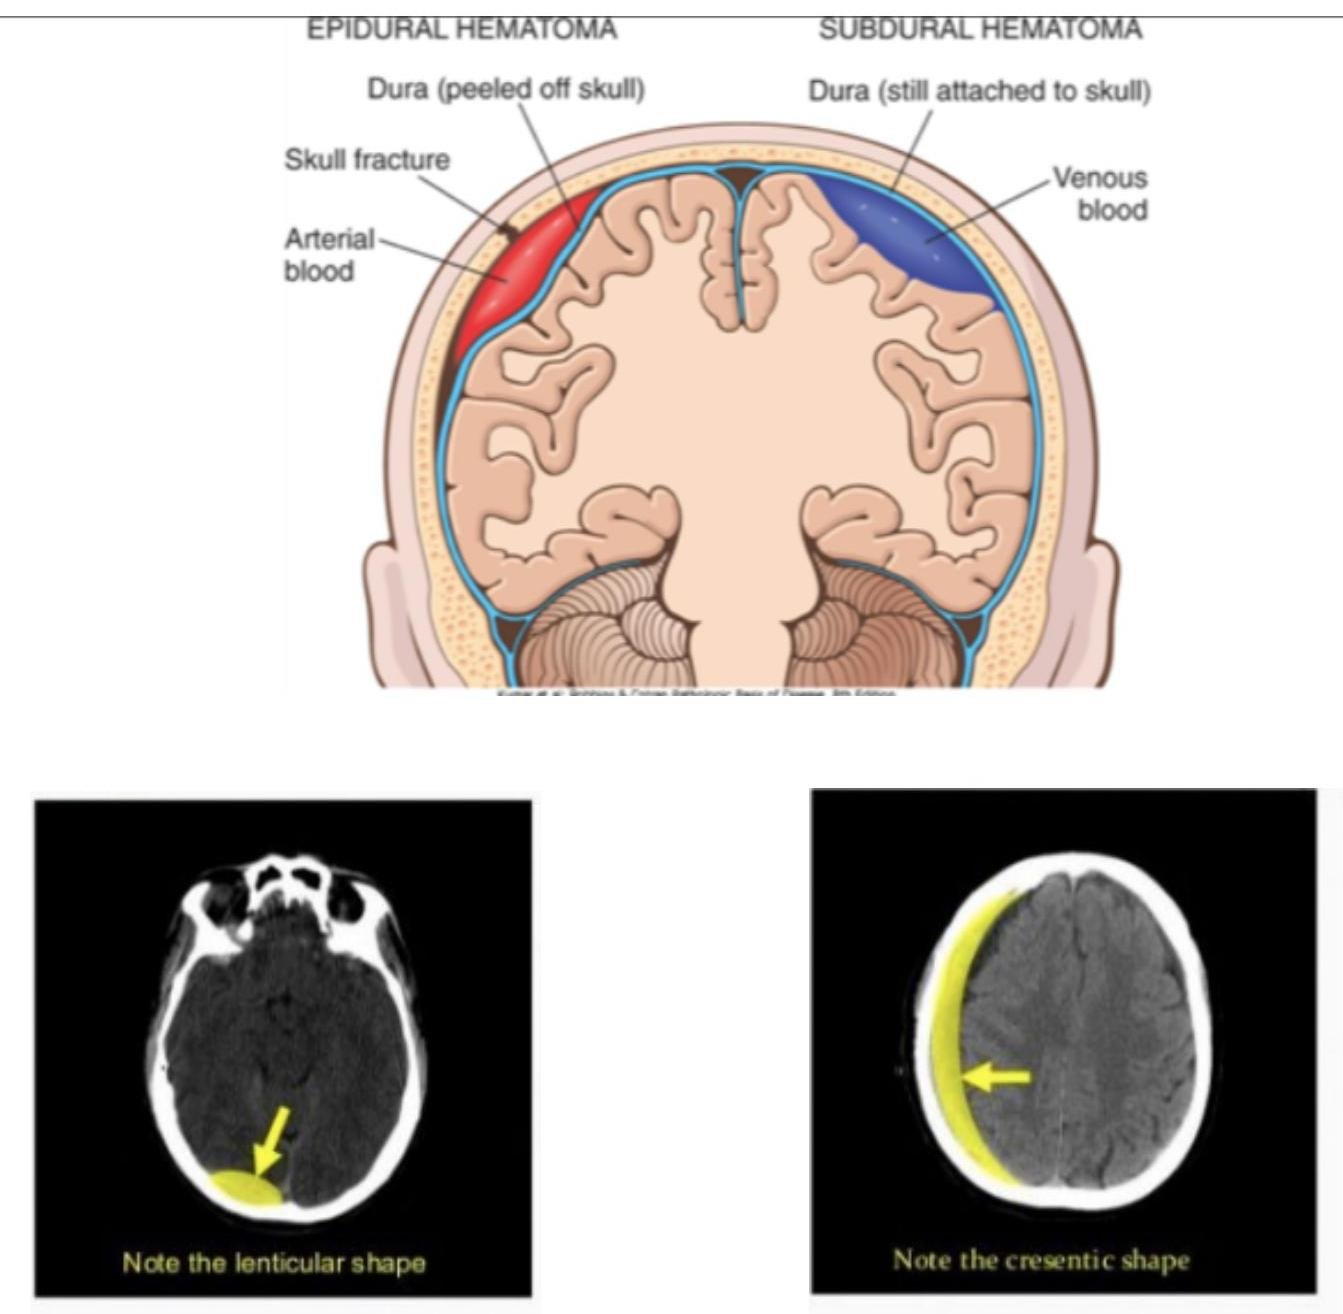

# TRAUMATISMO CRANEOENCEFÁLICO ## DEFINICIÓN Es una lesión directa en el cráneo, encéfalo o meninges por efecto mecánico provocado por un agente externo. Se clasifica en tres tipos: | TCE LEVE | Glasgow 14-15 | Cefalea leve, menos de 3 vómitos, sin pérdida de la conciencia | | :--------------: | :---------------------------------------------: | :----------------------------------------------------------------: | | TCE MODERADO | Glasgow 9-13 | Cefalea intensa, más de 3 vómitos, pérdida del estado de alerta, alteración de la conciencia, amnesia postraumática, convulsiones, sospecha de maltrato infantil, politraumatizado o trauma facial | | TCE GRAVE | Glasgow 8 o menor | Focalización, lesión penetrante del cráneo, fractura hundida o expuesta, disminución de Glasgow inicial, déficit neurológico de aparición posterior | **LESIÓN PRIMARIA**. Es el daño directo causado por el **impacto** del trauma o por los mecanismos de **aceleración-desaceleración**. Incluye **contusión cortical**, **laceración cerebral**, **fractura de cráneo**, **lesión axonal**, **contusión del tallo**, **desgarro dural o venoso**, etc. **LESIÓN SECUNDARIA**. Se desarrolla como consecuencia de la **injuria primaria**, desarrollando **sangrados**, **edemas**, **hiperemia**, **trombosis** y otros **procesos fisiopatológicos secundarios**. Incluye **hematoma intracraneano**, **epidural o subdural**, **edema cerebral**, **hipoxia y/o hipoperfusión cerebral**, elevación de **neurocitotoxinas** y **radicales libres**, **neuroinfección** y aumento de la **hipertensión endocraneana**. # EPIDEMIOLOGÍA - Es la causa más frecuente de coma (en ausencia de tumores o intoxicaciones). - Causa más frecuente de epilepsia en adolescentes y adultos jóvenes. ## FACTORES DE RIESGO - Causa y mecanismo de la lesión. - Tiempo transcurrido. - Estado mental subsecuente. - Presencia de crisis convulsivas postraumáticas. - Signos clínicos de fractura de cráneo. - Déficit neurológico específico. - Trastornos de la coagulación y uso de fármacos. - Sospecha de maltrato en menores de 18 años. ## ESCALA DE GLASGOW ADULTOS vs. NIÑOS | RESPUESTA OCULAR | | Puntos | | :---------------: | :--------------: | :------: | | **ADULTOS** | **LACTANTE** | | | Espontánea | Espontánea | 4 | | A estímulos verbales | A estímulos verbales | 3 | | Al dolor | Al dolor | 2 | | Ausencia de respuesta | Ausencia de respuesta | 1 | | RESPUESTA VERBAL | | | | **ADULTOS** | **LACTANTE** | | | Orientado | Sonríe, arrulla, gorgorea | 5 | | Desorientado / Confuso | Llora apropiadamente | 4 | | Palabras incoherentes | Grita, llanto inadecuado | 3 | | Sonidos incomprensibles | Quejido - gruñido | 2 | | Ausencia de respuesta | Sin respuesta | 1 | | RESPUESTA MOTORA | | | | **ADULTOS** | **LACTANTE** | | | Obedece órdenes | Adecuada al hablarle | 6 | | Localiza el dolor | Localiza el dolor | 5 | | Retira lo que le causa dolor | Retira lo que le causa dolor | 4 | | Flexión anormal | Flexión anormal | 3 | | Extensión anormal | Extensión anormal | 2 | | Ausencia de respuesta | Ausencia de respuesta | 1 | # MANEJO INICIAL DEL TCE ## TRAUMA LEVE (GLASGOW 14-15) Evaluación: Una vez documentado que se trata de un paciente con **TCE Leve**, se sabe que el riesgo de **complicaciones** es mínimo, por lo que el paciente no amerita **manejo intrahospitalario**. Monitorización: La **vigilancia** estará a cargo de los padres o **custodios** del menor en **DOMICILIO**. - La vigilancia de 6 horas en hospital es a criterio de decisión del médico. - No existe evidencia de que deba impedirse el **sueño** en las horas posteriores (incluso la falta de sueño puede modificar la conducta del paciente, dificultando la vigilancia de **datos de alarma**). - Se sugiere despertarlo cada 3 horas para evaluarlo. Indicaciones de una **NUEVA VALORACIÓN** (datos de alarma): - 3 o más vómitos en 24 horas. - Cefalea intensa. - Imposibilidad para establecer o mantener estado de despierto. - Crisis convulsivas. - Cambios en la conducta del menor. - Cualquier déficit neurológico (amaurosis, amnesia, paresia). - Presencia de hemorragia o salida de líquido por nariz u oído. - Marcha tambaleante o posturas anormales. TRAUMA MODERADO (GLASGOW 9-13) **VALORACIÓN E INVESTIGACIÓN EN URGENCIAS**: - **ABC**. - Deben ser valorados en un tiempo máximo de 15 minutos. - Si clínicamente se evidencia una lesión cerebral o de columna cervical, la valoración debe ser extensa. Criterios para realizar **RX**: - Menores de 1 año. - Sospecha de maltrato (complementar con huesos largos). - Pérdida de conciencia superior a cinco minutos (solo si no hay TAC). - Crepitaciones o hundimiento. - Trauma facial grave. - Rx Cervical indicada si hay politraumatismo, TCE Grave, dolor cervical (proyección antero-posterior). - No deben ser usadas como diagnóstico, solo de apoyo. # CRITERIOS PARA TAC INMEDIATA - Pérdida de conciencia de más de 5 minutos. - Amnesia anterógrada o retrógrada de más de 5 minutos. - Letargia. - 3 o más vómitos. - Convulsiones postraumáticas (sin antecedente de epilepsia). - Glasgow <15 en menores de 1 año y Glasgow <14 en el resto de pediátricos. - Sospecha de lesión abierta o deprimida (fontanela tensa). - Cualquier signo de fractura de base del cráneo. - Déficit neurológico focal. - Si es menor de un año: hematoma, edema, laceración de +5 cm en cabeza. - Mecanismo peligroso: accidente de alta velocidad, caída mayor a 3 metros, daño de alta velocidad con proyectil. - Coagulopatía (antecedente de sangrado o anticoagulantes). ## CRITERIOS PARA RMN: - No se indica como método primario de investigación para lesión cerebral secundaria a TCE. - Puede otorgar información adicional para el pronóstico (detecta lesiones pequeñas que no se ven en TAC). ## CRITERIOS PARA INTUBACIÓN EN TCE PEDIÁTRICO: - Escala de coma de Glasgow menor a 10 (adultos < 8). - Disminución de Glasgow de +3 puntos posterior a una calificación inicial. - Coma. - Anisocoria > 1 mm. - Lesión cervical espinal que comprometa ventilación. - Apnea. - Pérdida de reflejos de protección laríngea. - Hipercapnia (PaCO2 > 45 mmHg) o Hipoxemia (PaO2 < 60 mmHg). - Hiperventilación espontánea que ocasione PaCO2 < 25 mmHg. ## ESTABILIZACIÓN CIRCULATORIA - Determinación de FC, TA, calidad de pulsos centrales, periféricos y llenado capilar. - **Reanimación agresiva con fluidos** es necesaria si hay hipotensión. - - **CRISTALOIDES ISOTÓNICOS** 20 ml/kg (Cloruro de Sodio 0.9%). ○ No usar hipotónicos (Solución glucosada o Agua Inyectable) para reanimación inicial. - La TA mínima (percentil 5) para niños se obtiene = **70 + (Edad en Años x 2)**. - No se recomienda usar diuréticos. # HEMATOMA EPIDURAL - Consiste en la **acumulación de sangre** entre el **cráneo y la duramadre**. - Representa el 2-4 % de los traumas que requieren hospitalización. - Es más común en **niños, jóvenes y adultos jóvenes** (entre más edad, la **duramadre** está más pegada al hueso). ## ETIOLOGÍA 1. **SANGRADO ARTERIAL** (75-95% asociado a **fracturas**) → 70 % región **TEMPORAL**. a. **ARTERIA MENÍNGEA MEDIA**. 2. **Sangrado Venoso** (15%). ## CLÍNICA 1. **Pérdida de conciencia y luego periodo lúcido**, posterior **deterioro neurológico** (50 % de los casos). 2. Cefalea, vómito, hemiparesia, deterioro de alerta. 3. **Coma**. 4. **Herniación**. 5. **Muerte**. **TRIADA DE CUSHING** (Hipertensión Intracraneana) Sucede cuando el **efecto de masa** aumenta la **PIC**: **Hipertensión** + **Bradicardia** + **Alteraciones Respiratorias**. ## DIAGNÓSTICO **TOMOGRAFÍA COMPUTARIZADA**: Hallazgos: Forma de **LENTE BICONVEXA** + (puede) **Desplazamiento de línea media** (en los exámenes lo pueden mencionar como forma de **naranja o limón**). ## TRATAMIENTO ## QUIRÚRGICO:  El paciente puede estar asintomático; el **tratamiento quirúrgico** será en los que el **desplazamiento de la línea media** sea **significativo** (**efecto de masa > 10 mm**). **CIRUGÍA - CRANEOTOMÍA + DRENAJE DE HEMATOMA** (se realiza **evacuación y hemostasia**). Si hay **Hipertensión Intracraneana** - **Manitol al 20 %**. ## PRONÓSTICO La **Mortalidad** es del **5%**. - Si se presenta en región **TEMPORAL** es **más peligroso** que el parietal debido al riesgo de **herniación** (puede empujar el lóbulo temporal y formar una **hernia uncal**). # HEMATOMA SUBDURAL - Originado por una **LESIÓN EN PLEXOS VENOSOS SUBDURALES Y VENAS PUENTE** que comunican hacia los senos venosos durales, es decir, **debajo de la duramadre** y **antes de la aracnoides**. Es **más frecuente en la población adulta mayor** (poco común en niños). **Localización más frecuente** - **Fronto-Temporal**. ## ETIOLOGÍA 1. **Contusiones cerebrales** (50%). 2. **Hemorragia subaracnoidea** (25%). La causa más común son las **caídas desde su propia altura**. 3. **Hematomas epidurales** (10%). ## FISIOPATOLOGÍA 1. **Acumulación de sangre** alrededor de **laceración del parénquima**. 2. **RUPTURA DE VENAS PUENTE** por **mecanismo de aceleración-desaceleración**. 3. **Lesión arterial** - **MUY RARO** (puede ser por **ruptura de aneurisma**). ## CLASIFICACIÓN - Agudo: 1-3 días (TAC Hiperdensa). - Subagudo: 4-14 días (TAC Isodensa). - Crónico: +15 días (TAC Hipodensa). ## CLÍNICA - **Dolor de cabeza**. - **Cambios en el estado mental**. - **Hemiparesia contralateral**. - **Focalización neurológica**. - **Pseudodemencia en ancianos**. # DIAGNÓSTICO ## Tomografía Computarizada ## Hallazgos: - Imagen en **Semiluna (Falciforme)** que sigue el contorno del cerebro. - (En los exámenes lo pueden mencionar como **banana**). ## TRATAMIENTO  QUIRÚRGICO: - Se realiza una **evacuación del hematoma + lavado + hemostasia + drenaje subgaleal**. ## PRONÓSTICO ## MAL PRONÓSTICO - **Hipotensión arterial**. - **Mayores de 60 años**. - **Glasgow menor a 6**. **MORTALIDAD** 50%. - **Hematomas de > 10 mm de espesor**. - **Desviación línea media mayor a 5 mm**. # EPIDURAL vs. SUBDURAL  EPIDURAL SUBDURAL # FRACTURA DE LA BASE DEL CRÁNEO Es importante evaluar las **fracturas craneales** ya que son **marcadores de intensidad** y **sugieren lesión intracraneal**. Las fracturas que presenten **fragmentos de hueso deprimido** necesitarán **reparación quirúrgica**. ## CLÍNICA - **Hemotímpano**. - Lesión de **PC** (Anosmia, PCI Frontoetmoidales, PC VII yd VIII por fracturas del peñasco y del VI par en las fracturas del clivus). - **Otorrea**. - **Epistaxis**.  | BASE ANTERIOR | **Equimosis periorbitaria (Ojos de Mapache)** y **Rinorraquia** | | :-------------: | :------------------------------------------------------------ | | BASE MEDIA | **Equimosis retroauricular (Signo de Battle)** y **Otorraquia** | | BASE POSTERIOR | Cuadro clínico no definido, se visualiza por **TAC** | ## DIAGNÓSTICO ## TOMOGRAFÍA COMPUTARIZADA - Se debe realizar en **TCE Moderado y Severo** para descartar lesiones. ## TRATAMIENTO - Conservador. # CONMOCIÓN CEREBRAL ## CLÍNICA - **Alteración del nivel de conciencia transitoria y duración variable**. - **Amnesia del episodio**. - **Incoordinación**. ## DIAGNÓSTICO - **TAC sin alteración radiológica**. ## TRATAMIENTO No precisa tratamiento específico. ## CONTUSIÓN CEREBRAL Corresponde al 9% de los TCE, por **mecanismos de golpe y contragolpe** (pueden ser **hemorrágicos o no**). ## CLÍNICA - Variable y limitado deterioro del estado neurológico. - Su comportamiento es **amenazante entre el día 4 y 7** debido al **efecto de masa** por la **contusión y el edema** con pico. ## DIAGNÓSTICO - **TAC** que evidencia **lesiones intraparenquimatosas hiperdensas pequeñas**. ## TRATAMIENTO - **Cirugía** dependiendo de la localización, tamaño y el estado neurológico del paciente. - **Anticonvulsivante profiláctico**. # LESIÓN AXONAL DIFUSA Traduce la suma de un concepto clínico (**coma traumático prolongado**) y un concepto anatomopatológico (**alteración del citoesqueleto**, con **degeneración del axón** y **desconexión del mismo o axotomía**). Tras el **TCE**, la **secuencia fisiopatogénica** sería una **primitiva excitación neuronal** seguida de una **inhibición**, produciéndose la **pérdida de conciencia** y la **liberación masiva de iones al medio extracelular**. ## CLÍNICA **Deterioro precoz y mantenido del nivel de conciencia**. ## DIAGNÓSTICO - **TAC de aspecto aparentemente normal**. ## TRATAMIENTO **Conservador**.  # MANEJO TCE NIÑOS  # EVALUACIÓN INICIAL TCE ADULTOS  # MANEJO TCE ADULTOS  # MÉTODOS DIAGNÓSTICOS ADULTOS

# TRAUMATISMO CRANEOENCEFÁLICO ## DEFINICIÓN Es una lesión directa en el cráneo, encéfalo o meninges por efecto mecánico provocado por un agente externo. Se clasifica en tres tipos: | TCE LEVE | Glasgow 15- 14 | Cefalea Leve Menos de 3 vómitos Sin pérdida de la conciencia | | :--: | :--: | :--: | | TCE MODERADO | Glasgow 13 - 9 | Cefalea intensa Más de 3 vómitos Pérdida del estado de alerta Alteración de la conciencia Amnesia post-traumática Convulsiones Sospecha de maltrato infantil Politraumatizado o trauma facial | | TCE GRAVE | Glasgow 8 o menor | Focalización Lesión penetrante del cráneo Fractura hundida o expuesta Disminución de Glasgow inicial Déficit neurológico de aparición posterior | LESIÓN PRIMARIA. Es el daño directo causado por el impacto del trauma o por los mecanismos de aceleracióndesaceleración. Incluye contusión cortical, laceración cerebral, fractura de cráneo, lesión axonal, contusión del tallo, desgarro dural o venoso, etc. LESIÓN SECUNDARIA. Se desarrolla como consecuencia de la injuria primaria, desarrollando sangrados, edemas, hiperemia, trombosis y otros procesos fisiopatológicos secundarios. Incluye hematoma intracraneano, epidural o subdural, edema cerebral, hipoxia y/o hipoperfusión cerebral, elevación de neurocitotoxinas y radicales libres, neuroinfección y aumento de la hipertensión endocraneana # EPIDEMIOLOGÍA - Es la causa más frecuente de coma (en ausencia de tumores u ocupacional) - Causa más frecuente de epilepsia en adolescentes y adultos jóvenes. ## FACTORES DE RIESGO - Causa y mecanismo de la lesión - Tiempo transcurrido - Estado mental subsecuente - Presencia de crisis convulsivas postraumáticas - Signos clínicos de fractura de cráneo - Déficit neurológico específico - Trastornos de la coagulación y uso de fármacos - Sospecha de maltrato en menores de 18 años ## ESCALA DE GLASGOW ADULTOS V NIÑOS | RESPUESTA OCULAR | | Puntos | | :--: | :--: | :--: | | ADULTOS | LACTANTE | | | Espontánea | Espontánea | 4 | | A estímulos Verbales | A estímulos Verbales | 3 | | Al dolor | Al dolor | 2 | | Ausencia de respuesta | Ausencia de respuesta | 1 | | RESPUESTA VERBAL | | | | ADULTOS | LACTANTE | | | Orientado | Sonríe, arrulla, gorgorea | 5 | | Desorientado / Confuso | Llora apropiadamente | 4 | | Palabras Incoherentes | Grita, llanto inadecuado | 3 | | Sonidos Incomprensibles | Quejido - gruñido | 2 | | Ausencia de Respuesta | Sin respuesta | 1 | | RESPUESTA MOTORA | | | | ADULTOS | LACTANTE | | | Obedece órdenes | Adecuada al hablarle | 6 | | Localiza el dolor | Localiza el dolor | 5 | | Retira lo que le causa dolor | Retira lo que le causa dolor | 4 | | Flexión Anormal | Flexión Anormal | 3 | | Extensión Anormal | Extensión Anormal | 2 | | Ausencia de respuesta | Ausencia de respuesta | 1 | # MANEJO INICIAL DEL TCE ## TRAUMA LEVE (GLASGOW 14-15) Evaluación: una vez documentado que se trata de un paciente con TCE Leve, se sabe que el riesgo de complicaciones es mínimo por lo que el paciente no amerita manejo intrahospitalario. Monitorización: vigilancia estará a cargo de los padres o custidos del menor en DOMICILIO. - La vigilancia de 6 horas en hospital es a criterio de decisión del médico - No existe evidencia de que deba impedirse el sueño en las horas posteriores (incluso la falta de sueño puede modificar la conducta del paciente, dificultando la vigilancia de datos de alarma) - Se sugiere despertarlo cada 3 horas horas para evaluarlo Indicaciones de una NUEVA VALORACIÓN (datos de alarma) - 3 o más vómitos en 24 horas - Cefalea intensa - Imposibilidad para establecer o mantener estado de despierto - Crisis convulsivas - Cambios en la conducta del menor - Cualquier déficit neurológico (amaurosis, amnesia, paresia) - Presencia de hemorragia o salida de líquido por nariz.u oído - Marcha fambaleante o posturas anormales. TRAUMA MODERADO (GLASGOW 9 - 13) VALORACIÓN E INVESTIGACIÓN EN URGENCIAS: ## - ABC - Deben ser valorados en un tiempo máximo de 15 minutos - Si clínicamente se evidencia una lesión cerebral o de columna cervica, la valoración debe ser extesna, Criterios para realizar RX - Menores de 1 año - Sospecha de maltrato (complementar con huesos largos) - Pérdida de conciencia superir a cinco minutos (solo si no hay TAC) - Crepitaciones o hundimiento - Trauma facial grave - Rx Cervical indicada si hay lesiones politrauma, TCE Grave, dolor cervical (proyección antero-posterior - No deben ser usadas como diagnóstico, solo de apoyo. # CRITERIOS PARA TAC INMEDIATA - Pérdida de conciencia de +5 minutos - Amnesia anterógrada o retrógrada de +5 minutos - Letargia \Rightarrow 3 o más vómitos - Convusliones post traumáticas (Sin antecedente de epilepsia) - Glasgow <15 en menores de 1 año y Glasgow <14 en el resto de pediátricos - Sospecha de lesión abierta o deprimida (fontanela tensa) - Cualquier signo de fractura de base del cráneo - Déficit neurológico focal - Si es menor de un año: hematoma, edema, laceración de +5 cm en cabeza - Mecanismo peligroso: accidente alta velocidad, caída mayor a 3 metros, daño de alta velocidad con proyectil - Coagulopatía (antecedente de sangrado o anticoagulantes) ## CRITERIOS PARA RMN: - No se indica como método primario de investigación para lesión cerebral secundaria a TCE - Puede otorgar información adicional para el pronóstico (detecta lesiones pequeñas que no se ven en TAC) ## CRITERIOS PARA INTUBACIÓN EN TCE PEDIÁTRICO: - Escala de coma de Glasgow menor a 10 (adultos 8) - Disminución de Glasgow de +3 puntos posterior a una calificación incial - Coma - Anisocoria +1 mm - Lesión cervical espinal que comprometa ventilación - Apnea - Pérdida de reflejos de protección laríngea - Hipercapina (PaCO2 +45mmHg) o Hipoxemia (PaCO2 -60mmHg) - Hiperventilación espontánea que ocasione PaCO2 - 25 mmHg ## ESTABILIZACIÓN CIRCULATORIA - Determinación de FC, TA, Calidad de pulsos centrales, periféricos y llando capilar - Reanimación agresiva con fluidos es necesaria si hay hipotensión - - CRISTALOIDES ISOTÓNICOS 20 ml / kg (Cloruro de Sodio 0.9%) ○ No usar hipotónicos (Sol glucosada o Agua Inyectable) para reanimación inicial - La TA mínima (percentil 5) para niños se obtiene =\mathbf{7 0}+ (Edad en Años x2) - No se recomienda usar diuréticos. # HEMATOMA EPIDURAL - Consiste en la acumulación de sangre entre el cráneo y la duramadre - Representa el 2-4 % de los traumas que requieren hospitalización. - Es más común en niños, jóvenes y adultos jóvenes (entre más edad, la duramadre está más pegada al hueso) ## ETIOLOGÍA 1. SANGRADO ARTERIAL (75-95% asociado a fracturas) \rightarrow 70 % región TEMPORAL. a. ARTERIA MENÍNGEA MEDIA 2. Sangrado Venoso (15%) ## CLÍNICA 1. Pérdida de conciencia y luego periodo lúcido, posterior deterioro neurológico ( 50 % de los casos) 2. Cefalea, vómito, hemiparesia, deterioro de alerta 3. Coma 4. Herniación 5. Muerte TRIADA DE CUSHING (Hipertensión Intracraneana) Sucede cuando el efecto de masa aumenta la PIC Hipertensión + Bradicardia + Alteraciones Respiratorias ## DIAGNÓSTICO TOMOGRAFÍA COMPUTARIZADA: Hallazgos: Forma de LENTE BICONVEXA + (puede) Desplazamiento de línea media (en los exámenes lo pueden mencionar como forma de naranja o limón) ## TRATAMIENTO ## QUIRÚRGICO:  El paciente puede estar asintomático (el tratamiento Q x será en los que el desplazamiento de la línea media sea significativo - efecto de masa +10 mm ) CIRUGÍA - CRANEOTOMÍA + DRENAJE DE HEMATOMA (se realiza evacuación y hemostasia) Si hay Hipertensión Intracraneana - Manitol al 20 % ## PRONÓSTICO Mortalidad es del 5% - Si se presenta en región tempral es más peligroso que el parietal debido al riesgo de herniación (puede empujar el lóbulo temporal y formar una hernia uncal) # HEMATOMA SUBDURAL - Originado por una LESIÓN EN PLEXOS VENOSOS SUBDURALES Y VENAS PUENTE que comunican hacia los senos venosos durales, es decir, debajo de la duramadre y antes de la aracnoides. Es más frecuente en la población adulta mayor (poco común en niños) Localización más frecuente - Fronto-Temporal ## ETIOLOGÍA 1. Contusiones cerebrales (50%) 2. Hemorragia subaracnoidea (25%) La causa más común son las caídas desde su propia altura 3. Hematomas epidurales (10%) ## FISIPATOLOGÍA 1. Acumulación de sangre alrededor de laceración del parénquima 2. RUPTURA DE VENAS PUENTE por mecanismo de aceleración-desaceleración 3. Lesión arterial - MUY RARO (puede ser por ruptura de aneurisma) ## CLASIFICACIÓN - Agudo: 1-3 días (TAC Hiperdensa) - Subagudo: 4-14 días (TAC Isodensa) - Crónico: +15 días (TAC Hipodensa) ## CLÍNCIA - Dolor de cabeza - Cambios en el estado mental - Hemiparesia Contralateral - Focalización neurológica - Pseudodemencia en ancianos # DIAGNÓSTICO ## Tomografía Computarizada ## Hallazgos: - Imagen en Semiluna (Falciforme) que sigue el contorno del cerebro. - (En los exámenos lo pueden mencionar como banana) ## TRATAMIENTO  QUIRÚRGICO: - Se realiza una evacuación del hematoma + lavado + hemostasia + drenaje subgaleal ## PRONÓSTICO ## MAL PRONÓSTICO - Hipotensión Arterial - Mayores de 60 años - Glasgow menor a 6 MORTALIDAD 50% - Hematomas de +10 mm de espesor - Desviación línea media mayor a 5 mm # EPIDURAL VS SUBDURAL  EPIDURAL SUBDURAL # FRACTURA DE LA BASE DEL CRÁNEO Es importante evaluar las fracturas craneales ya que son marcadores de intensidad y sugieren lesión intracraneal. Las fracturas que presenten fragmentos de hueso deprimido necesitarán reparación quirúrgica. ## CLÍNICA - Hemotímpano - Lesión de PC (Anosmia, PCI Frontoetmoidales, PC VII y VII por fracturas del peñasco y del VI par en las fracturas del clivus - Otorrea - Epistaxis  | BASE ANTERIOR | Equimosis Periorbitaria (Ojos de Mapache) y Rinorraquia | | :--: | :-- | | BASE MEDIA | Equimosis Retroauricular (Signo de Battle) y Otorraquia | | BASE POSTERIOR | Cuadro clínico no definido, se visualiza por TAC | ## DIAGNÓSTICO ## TOMOGRAFÍA COMPUTARIZADA - Se debe realizar en TCE Moderado y Severo para descartar lesiones. ## TRATAMIENTO - Conservador # CONMOCIÓN CEREBRAL ## CLÍNICA - Alteración del nivel de conciencia transitoria y duración variable - Amnesia del episodio - Incoordinación ## DIAGNÓSTICO - TAC sin alteración radiológica. ## TRATAMIENTO No precisa tratamiento específico ## CONTUSIÓN CEREBRAL Corresponde al 9% de los TCE, por mecanismos de golpe y contragolpe (pueden ser hemorrágico o no). ## CLÍNICA - Variable y limitado deterioro del estado neurológico - Su comportamiento es amenazante entre el día 4 y 7 debido al efecto de masa por la contusión y el edema con picos ## DIAGNÓSTICO - TAC que evidencia lesiones intraparenquimatosas hiperdensas pequeñas ## TRATAMIENTO - Cirugía dependiendo de la localización, tamaño y el estado neurológico del paciente - Aniconvulsivante profiláctico. # LESIÓN AXONAL DIFUSA (CONCUSIÓN) Traduce la suma de un concepto clínico (coma traumático prolongado) y un concepto anatomopatológico (alteración del citoesqueleto, con degeneración del axón y desconexión del mismo o axotomía). Tras el TCE la secuencia fisiopatogénica sería una primitiva excitación neuronal seguida de una inhibición, produciéndose la pérdida de conciencia y la liberación masiva de iones al medio extracelular. ## CLÍNICA Deterioro precoz y mantenido del nivel de conciencia ## DIAGNÓSTICO - TAC de aspecto aparentemente normal ## TRATAMIENTO Conservador.  # MANEJO TCE NIÑOS  # EVALUACIÓN INICIAL TCE ADULTOS  # MANEJO TCE ADULTOS  # MÉTODOS DIAGNÓSTICOS ADULTOS